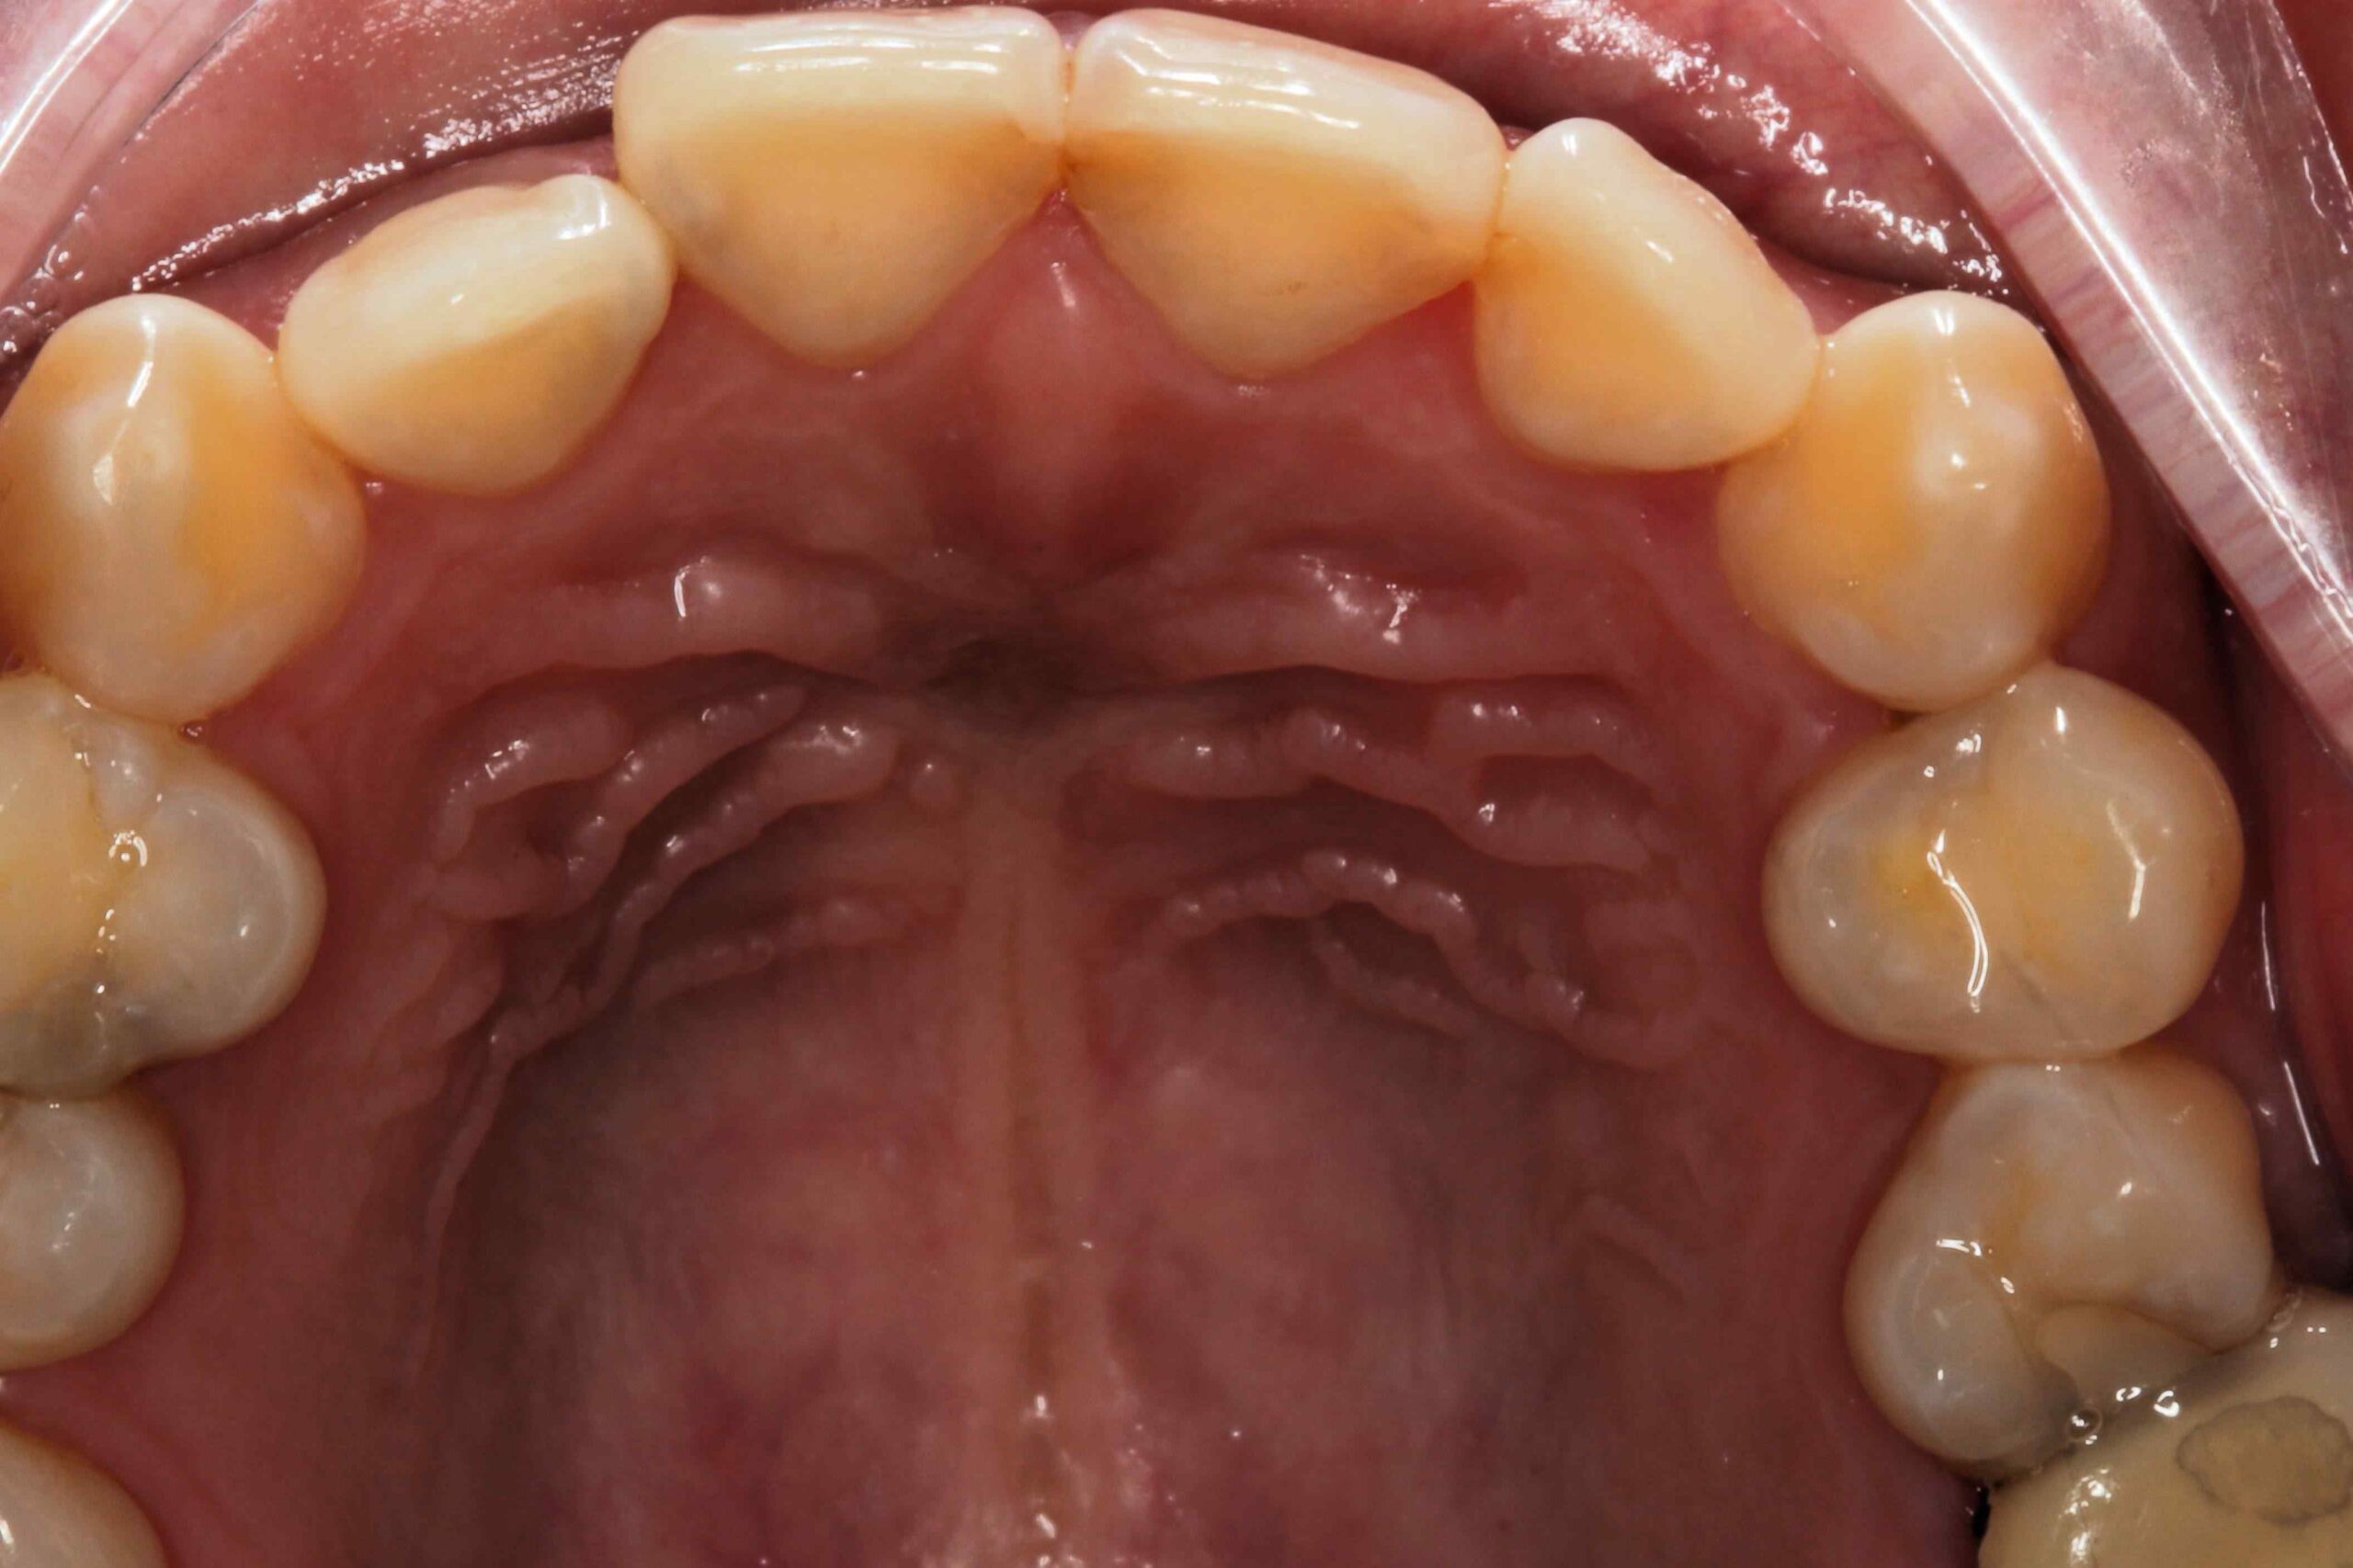

牙齒排列不整齊或琺瑯質發育不全,同樣容易使門牙蛀牙風險增加。參考中華民國牙醫師公會全國聯合會相關資訊。

當門牙蛀牙發生時,及時治療至關重要。治療方案依蛀牙嚴重程度而定,主要包括:

3.1 充填治療

對早期蛀牙進行充填,去除腐敗部分,再以填充材料修復蛀洞,恢復門牙功能與美觀。

3.2 根管治療

若蛀牙深入牙髓,則需進行根管治療,清除感染後填充根管,防止進一步擴散。

3.3 牙冠修復

對於損壞嚴重的門牙,製作陶瓷或樹脂牙冠以保護修復,既恢復功能又兼顧美觀。